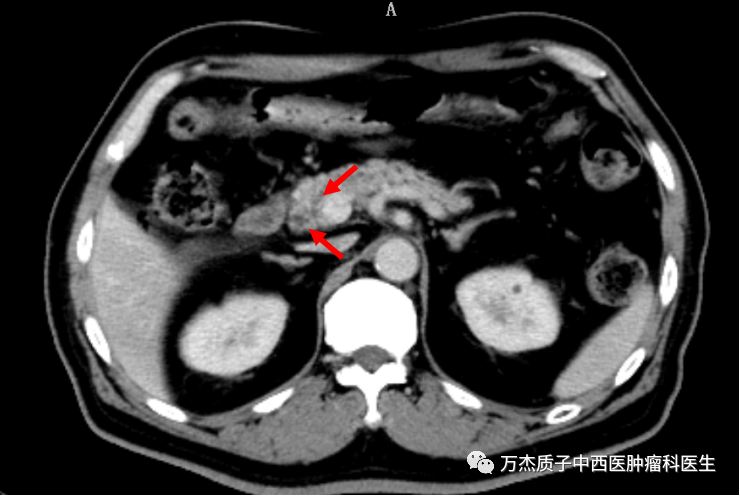

下图为质子治疗后半年复查的影像,显示肿瘤病灶缩小明显